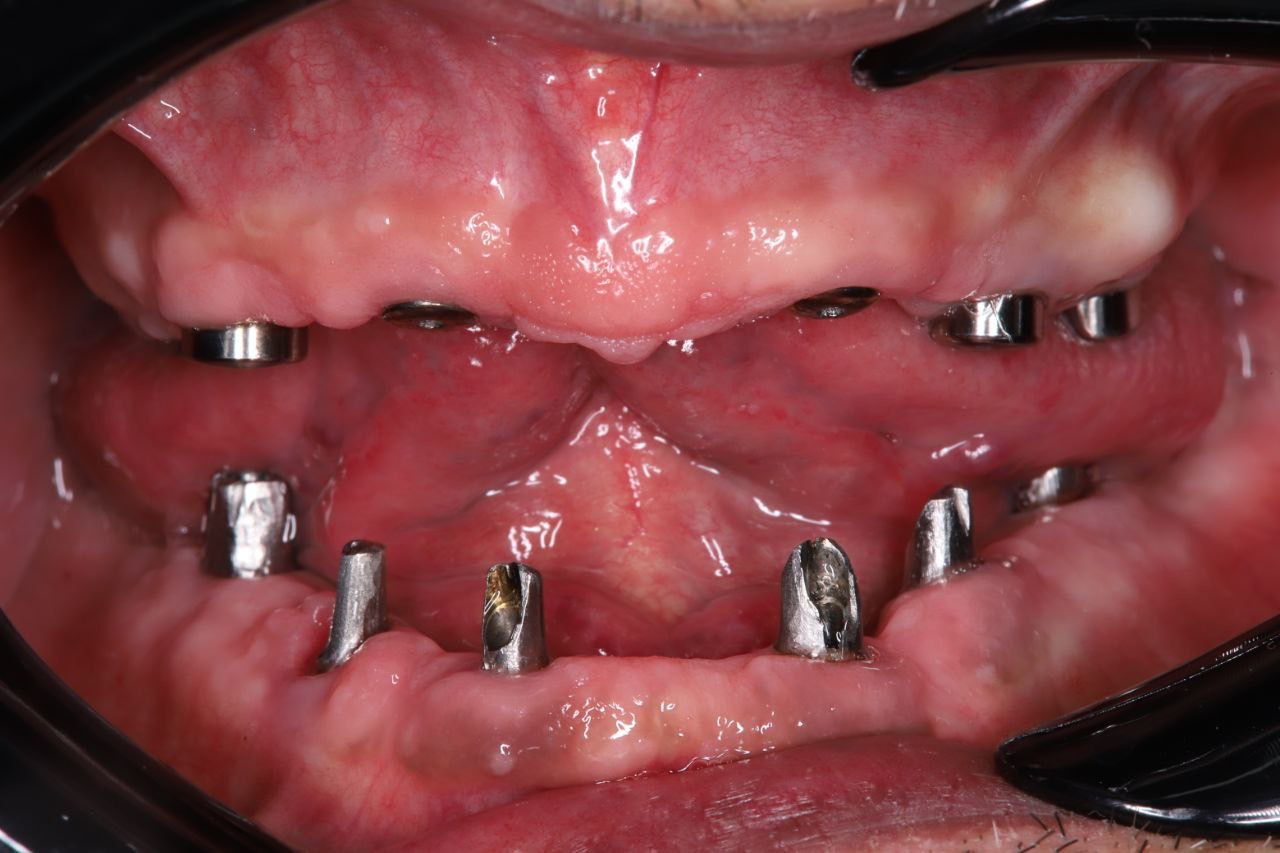

Пациент обратился с полным отсутствием зубов.

Проведена компьютерная диагностика и цифровое планирование лечения. Принято решение о восстановлении зубного ряда с опорой на импланты.

Установлено 6 дентальных имплантов. После хирургического этапа были изготовлены и зафиксированы временные коронки (временная ортопедическая конструкция) на период приживления имплантов. После завершения остеоинтеграции изготовлены и установлены постоянные коронки из диоксида циркония.